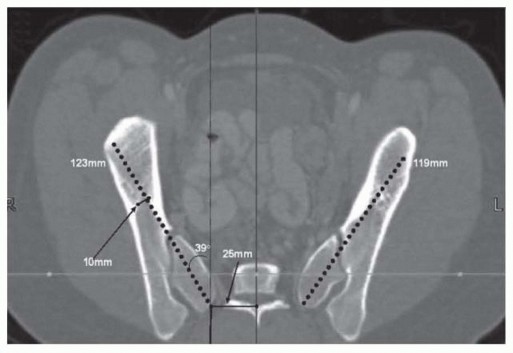

Pelvic Fixation for Neuromuscular Scoliosis DEFINITION Neuromuscular scoliosis (NMS) is a spinal deformity in…